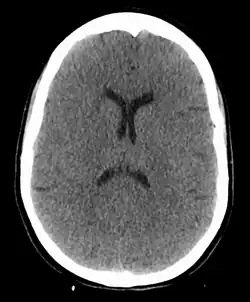

Anoxic brain injury following a hanging—both the loss of visible differentiation between grey and white matter and the reduced ventricle size due to brain swelling are visible

A hanging may induce one or more of the following medical conditions, some leading to death:

In the absence of fracture and dislocation, occlusion of blood vessels becomes the major cause of death, rather than asphyxiation. Obstruction of venous drainage of the brain via occlusion of the internal jugular veins leads to cerebral oedema and then cerebral ischemia. The face will typically become engorged and cyanotic (turned blue through lack of oxygen). Compromise of the cerebral blood flow may occur by obstruction of the carotid arteries, even though their obstruction requires far more force than the obstruction of jugular veins, since they are seated deeper and they contain blood in much higher pressure compared to the jugular veins.[25]